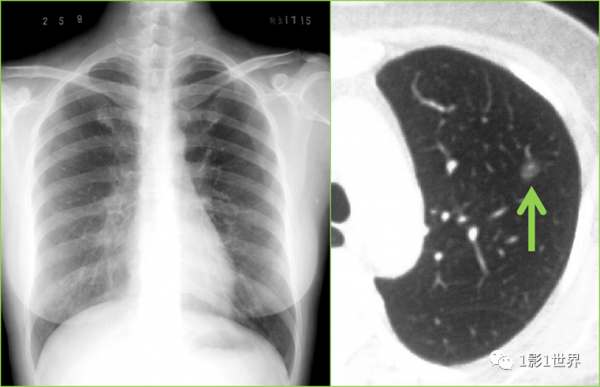

第一,未見異常,僅代表這種儀器、這種裝置未見異常,可能真沒事,也可能是這種裝置的侷限性。比如,最常用的胸部X線拍片,很多細小的病變真就顯不出來,只能報胸部正位片未見異常,但很多這種病人,在胸部CT底下,又會發現更多細小的問題。

胸部平片未發現異常,但是胸部CT發現左上肺磨玻璃結節